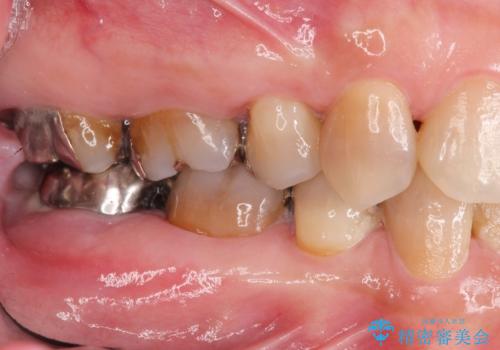

- ぐらぐらする歯や銀歯、なんとなくにおいのする奥歯の治療を求めて来院されました。

X線、歯周組織検査の結果、全体的に奥歯には重度〜中等度の歯周病の問題が見られました。

残すことのできない歯、予後の悪い歯を抜去し、ブリッジイ・ンプラントによる機能回復をおこなっていくと同時に、残すことのできる歯には歯周病治療をしっかりと行い、

将来に渡りしっかりと自分の歯で噛めるような口腔内環境を構築していきます。